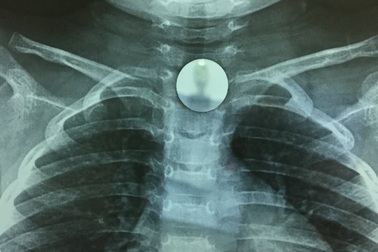

Gắp đồng xu có đường kính hơn 2cm từ thực quản bé gáiVừa ngậm đồng xu trong miệng, vừa trêu đùa với bạn, không may cháu Nguyễn Thị Q. N. (trú phường Kỳ Thịnh, thị xã Kỳ Anh, Hà Tĩnh) nuốt vào cổ. Sau khi được đưa vào bệnh viện, các bác sĩ tiến hành soi gắp thành công đồng xu có đường kính 2,3cm từ thực quản của cháu N.